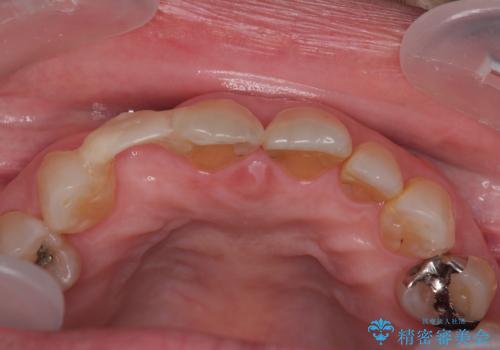

仮歯を事前に用意し、インプラント埋入時に即日で仮歯を装着する、即時荷重インプラントの計画で治療を進めて行くこととしました。

新幹線や飛行機を利用しても来院であり、極力来院回数を減らしたり、東京に用事があるタイミングに合わせてアポイントを調整したりと、負担が少なくなるようにして治療を進めて行きました。

来院間隔があいたため、予定よりも長くなりましたが、大きなトラブルもなく、外科処置は1回のみ、最小の来院数で無事に治療を終えることができました。